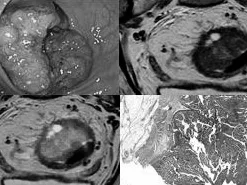

Rectal Cancer MRI Fellowship

This abdominal imaging fellowship will take participants through staging and restaging rectal cancer on MRI. Following a series of lectures, case readings, and discussions, Dr Stephanie Nougaret will share her vast knowledge on rectal cancer staging and restaging after neoadjuvant treatment.

Radiologists (to-be) who would like to become more confident on staging/restaging rectal cancer on MRI will find this abdominal imaging fellowship useful. This programme of 3 afternoons provides in-depth knowledge in the value of MRI during the management of rectal cancer.

Radiologists (to-be) will learn how to interpret staging and restaging MR images and deal with difficulties by evaluating numerous cases. After attending this course, the participants will not only be able to implement high-quality MR protocol in their own center but also will be able accurately interpret MR images both before and after neoadjuvant treatment.